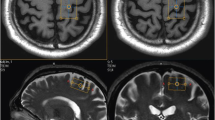

At baseline, significant increases of rCBF were observed bilaterally in the inferior parietal cortex (Brodmann area 40), stronger in the contralateral hemisphere with a maximum at 42 mm above the ACPC line. This cluster also extended into the superior parietal lobe (Brodmann area 7). Activation of the ipsilateral inferior parietal cortex was located between 34 and 48 mm above the ACPC line (Table 2, Fig. 1).

Activation during passive movements at baseline. Increases of regional cerebral blood flow (rCBF) during passive movements of the plegic (left) arm in stroke patients (passive movements vs. rest, within-group analysis, p < 0.01). Surface view of statistical parametric maps. All lesions were assigned to the right side of the brain. Three patients with a left-sided lesion were inverted about the midsagittal plane. Thus, for analytical purposes, the hemiplegic arm was always on the left. Areas of activation are superimposed onto a T1-weighted MRI brain scan